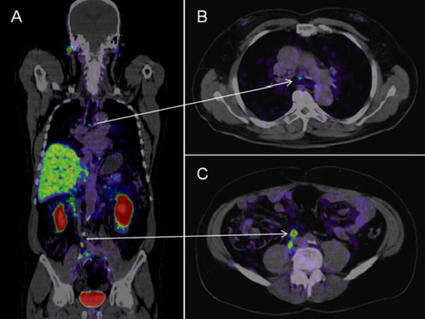

Series of PET/CT scans showing fewer tumors after Lu177-PSMA-617 treatment

PSMA-based PET scans of a man with prostate cancer at the beginning of treatment with Lu177-PSMA-617 (a) and after 6 cycles of the therapy (d).

Credit: Tijdschrift voor Urologie. August 2020. https://doi.org/10.1007/s13629-020-00300-z. CC-BY-4.0